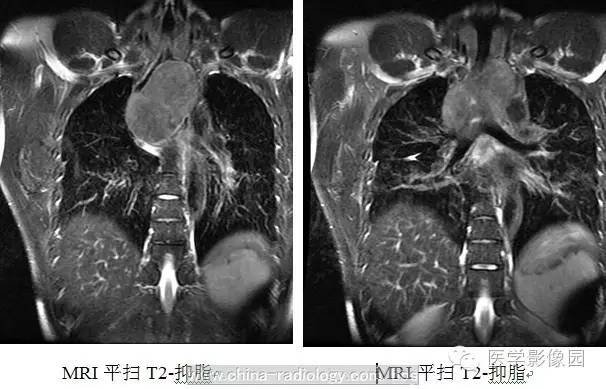

3、CT及磁共振(MRI)检查